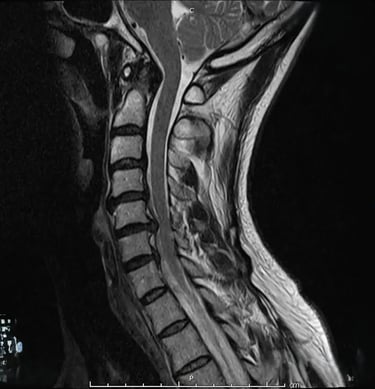

Cuando la hernia es cervical, puede generar:

- Dolor de cuello y rigidez

- Dolor que irradia al hombro, brazo o mano (cervicobraquialgia)

- Hormigueo/adormecimiento en dedos o mano

- Sensación de debilidad o pérdida de fuerza de agarre

- Molestias al mirar hacia abajo, usar móvil/ordenador o al dormir en ciertas posturas

- A veces, cefalea tensional asociada a la tensión cervical

Hernia discal cervical: síntomas más frecuentes